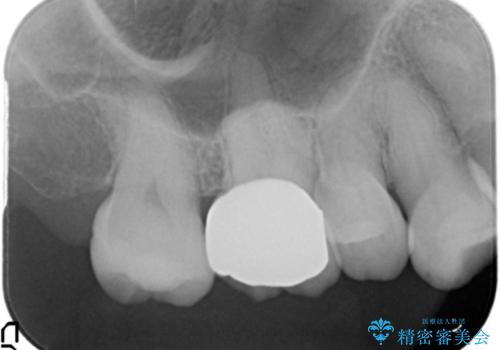

- 合計 19.8万円 右上7:セラミックインレー 7万円、右上6:ジルコニアクラウン10万円、仮歯1万円費用は治療当時の料金となります

右上6番は詰め物が大きく、インレーではなくクラウンとしました。